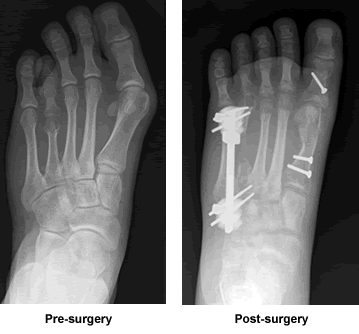

My left foot had been deformed my whole life. I was born with a large bunion and a toe that was about half the size it was supposed to be. I never showed my feet to anyone. I always wore closed toed shoes. Summer was my least favorite season...Even the getting out of school couldn't make up for the fact that I had to wear sneakers all the time and barely ever wanted to go swimming. Finally, I had had enough. I told my mom that I wanted to fix my foot. For several months, we went from doctor to doctor asking if anything could be done about my foot. The bunion was fine - everyone had seen something like that before - and all the doctors said it would not be too difficult to fix. The small toe, however, was a whole new issue altogether. Some doctors said they had no idea how to fix something like that. Others said it was impossible. Then, my mom came across Dr. Leavitt on the internet. She remembered hearing about him before, and we decided to go see him. I had basically given up hope by then, but my mom was feeling very optimistic.

When Dr. Leavitt saw my foot, he said he'd never done that type of surgery, but he did some research on it and found that it was entirely possible. And that was that. Several months later, he performed the surgery. He decided to take care of the bunion and the small toe at the same time. All we could do after that was wait while the toe bone grew and lengthened. Now, don't get me wrong, it wasn't just boring old waiting. It was tough. I was on crutches for six months. Plus, my foot hurt a lot for the first couple of months. Anytime it hurt more than usual, though, or even if I was just worried about it, Dr. Leavitt would tell me to come in either that day or the next. Even if it was a Sunday or he had a huge line of patients, he was always able to squeeze me in. Eventually, I found myself having to come into his office less and less, and, by the time I knew it, it was over. I finally was able to start walking and start wearing a shoe on my foot.

Now, it's if as I never had the surgery. I can run and wear high heels and do anything I could do before the surgery. The only difference is that my foot actually looks normal. I'm not afraid if other people see it anymore. Sure, I have some scars, but they're slowly fading. I'm actually excited for the summer to come around.